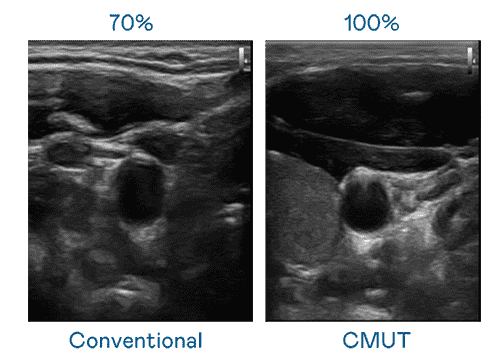

CMUT 技术是一种用电容式微机电元件来产生超音波讯号的技术。。。与传统 PZT 压电式技术相比,,,,CMUT 频宽增加 30%,,,,更宽频的超音波讯号让影像解析度大幅提升,,,,是实现高影像品质医疗超音波扫描、、、、促进精准医疗发展的关键技术。。

大频宽带来超清晰影像

超音波影像的解析度高低,,,首先取决于探头能发出的讯号频宽。。开云电子 CMUT 可提供高清晰的超音波讯号,,提供高频宽、、高灵敏度、、影像纹理细节更高的超音波影像,,协助医护人员缩短影像判读时间及利用精准的医疗影像进行诊断。。。